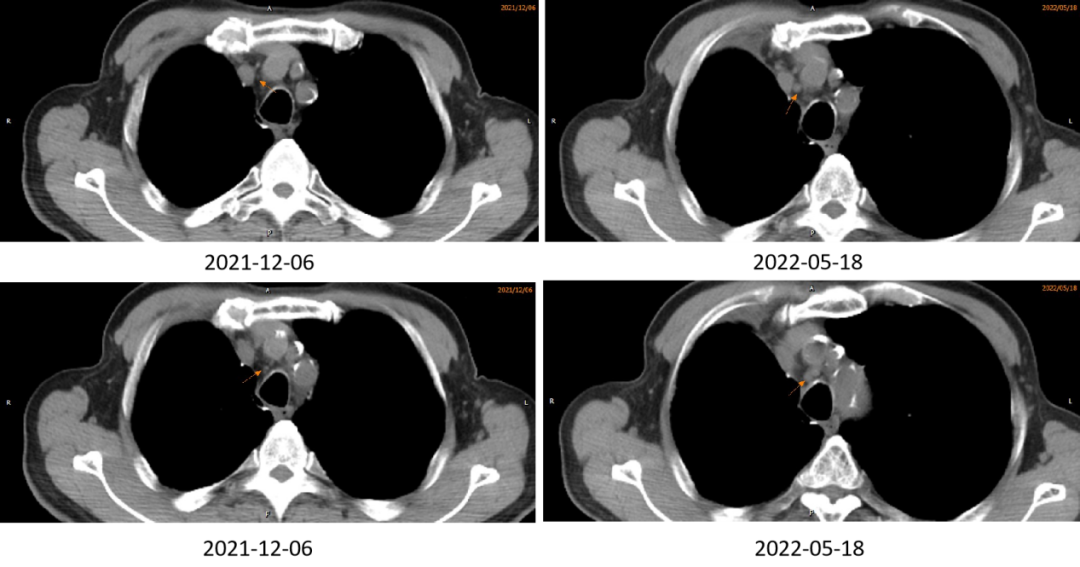

图7. 2022-05-18 CT:结合MRD随访考虑淋巴结转移

图9. 2022-08-27 CT:淋巴结明显缩小